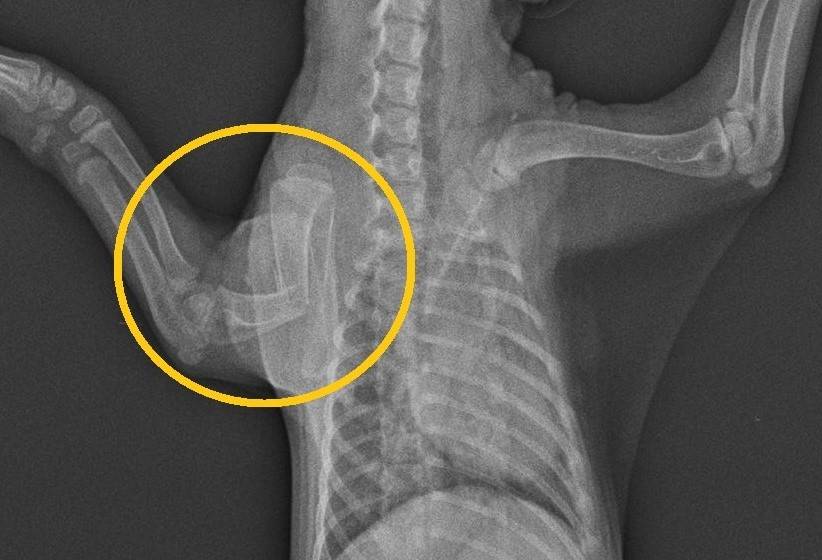

こちらの写真をご覧ください。

これは6月半ばに保護されたホンドタヌキのレントゲン写真です。

さあどこをケガしているでしょうか?

正解は・・・

はい、右上腕骨が骨折していました。見事にポッキリ折れてしまっています。

この個体はまだ体重が700gほどの子どものタヌキでした。